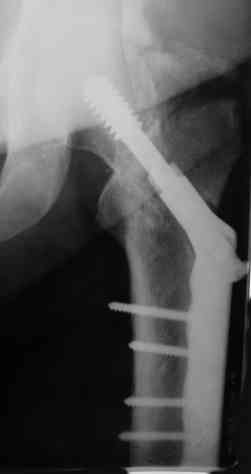

Пациентка 39 лет в декабре 2007г. в результате ДТП получила

оскольчатый метафизарный, Т-образный полный перелом мыщелков правого

бедра, базальный перелом шейки левого бедра. Перелом правого бедра лечили

аппаратом Илизарова, перелом шейки левого бедра синтезировали DHS.

Вставать на ноги начала ч\з 2 недели после операции с полной

нагрузкой на левую ногу, правую практически не нагружала. Через 7

месяцев появились боли в области левого тазобедренного сустава. На

контрольных снимках обнаружено не сращение шейки левого бедра.

появляющиеся при нагрузке. На контрольных Р-граммах имеется ложный

сустав шейки бедра, прорезывание головки относительно динамического

винта.